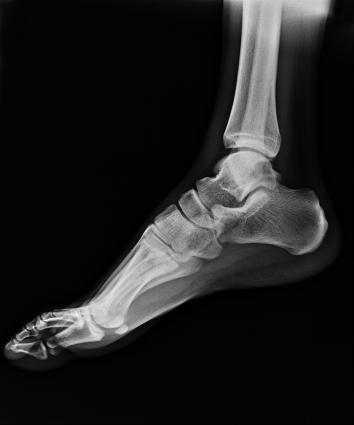

多功能動態(tài)平板DR,采用U型臂結(jié)構(gòu),具有靜態(tài)DR攝影、數(shù)字透視、數(shù)字造影和可視化攝影的功能。

滿足不同身高的受檢者快速地進(jìn)行胸片的靜態(tài)及動態(tài)檢查,適合大規(guī)模體檢。

SID可拉伸至1.8米,滿足標(biāo)準(zhǔn)胸片、職業(yè)性塵肺病檢查等特殊需求。